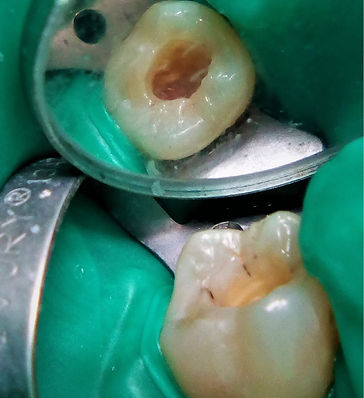

Seguono alcune foto.

Fig1. La cavità appena ripulita

Fig2. La terapia canalare all'inizio